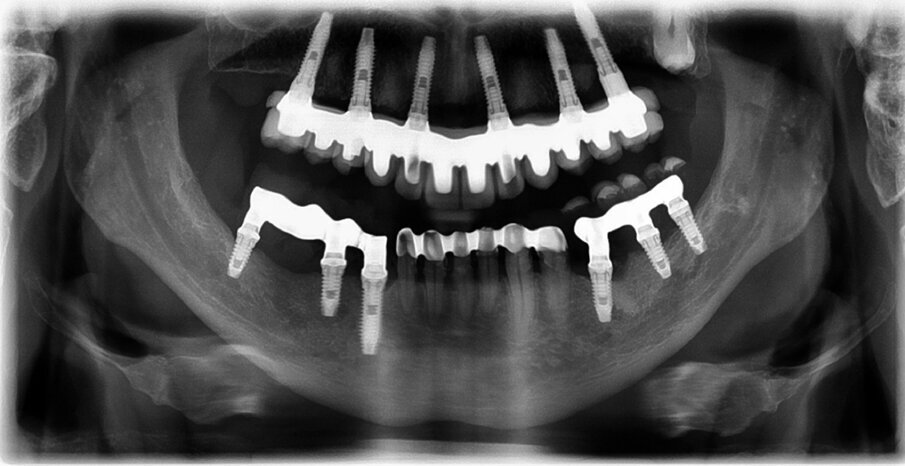

The finished restoration placed in the mouth showed good integration (Figs. 19 & 20). The correct implant seating was verified with a CT scan (Fig. 21). The basal adaptation was perfect to enable optimal cleaning of the mucosa. Occlusal fit was checked with active posterior cusps and canine and protrusive guidance.

Fig. 21: Radiograph after treatment.